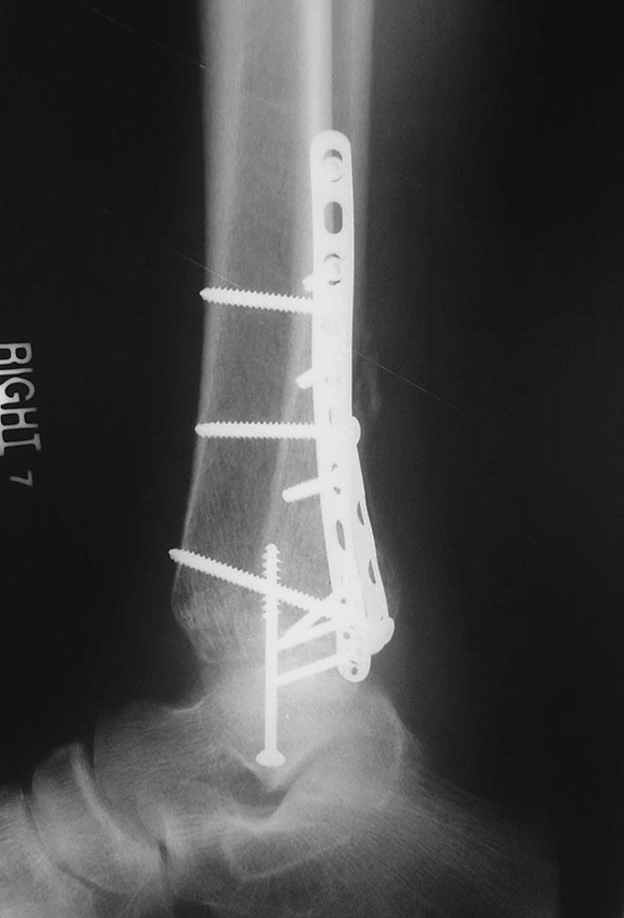

This is a pilon fracture. I suggest fixation of the fibula with a one-third tubular plate and a joint spanning external fixator on the medial side as initial treatment. If the tibial articular surface cannot be reconstituted, the patient will require an arthrodesis.

I would suggest to fix the fibular fracture at the very beginning and under fluoroscopical control and axial traction try to restore articular surface stabilizing percutanously by K wires and cannulated screws, type of external fixation to be used is up to your preference.

Второй случай сделан из одного разреза

Отправитель: Djoldas Kuldjanov, M.D. 16 Сентябрь 2004, 21:34

Pilon fracture: